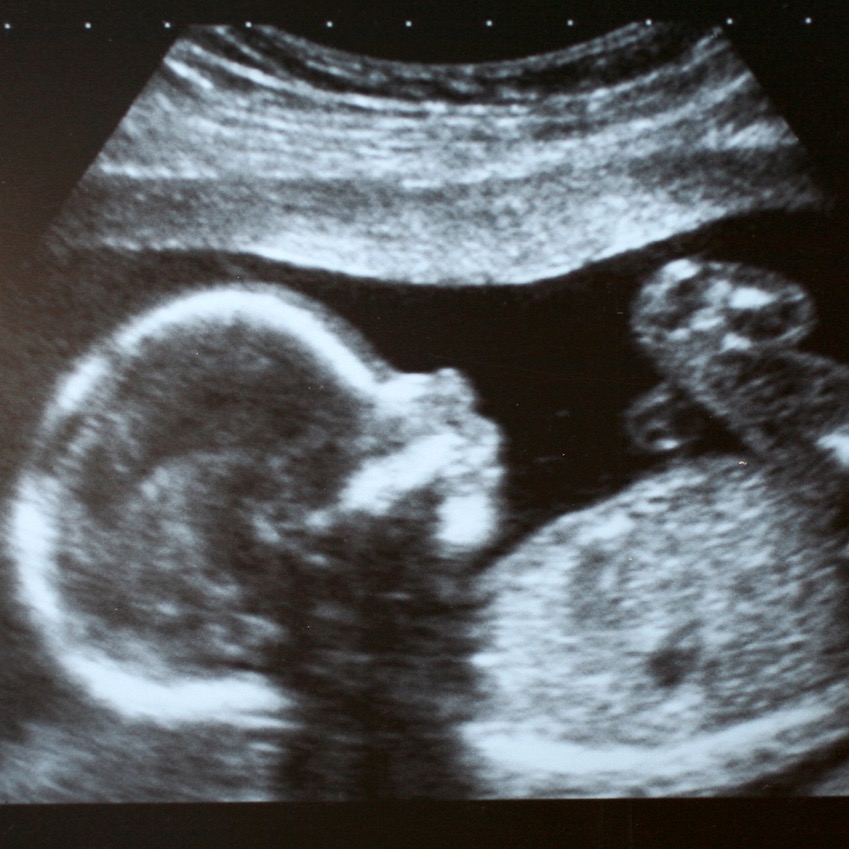

Скрининг 30 недель